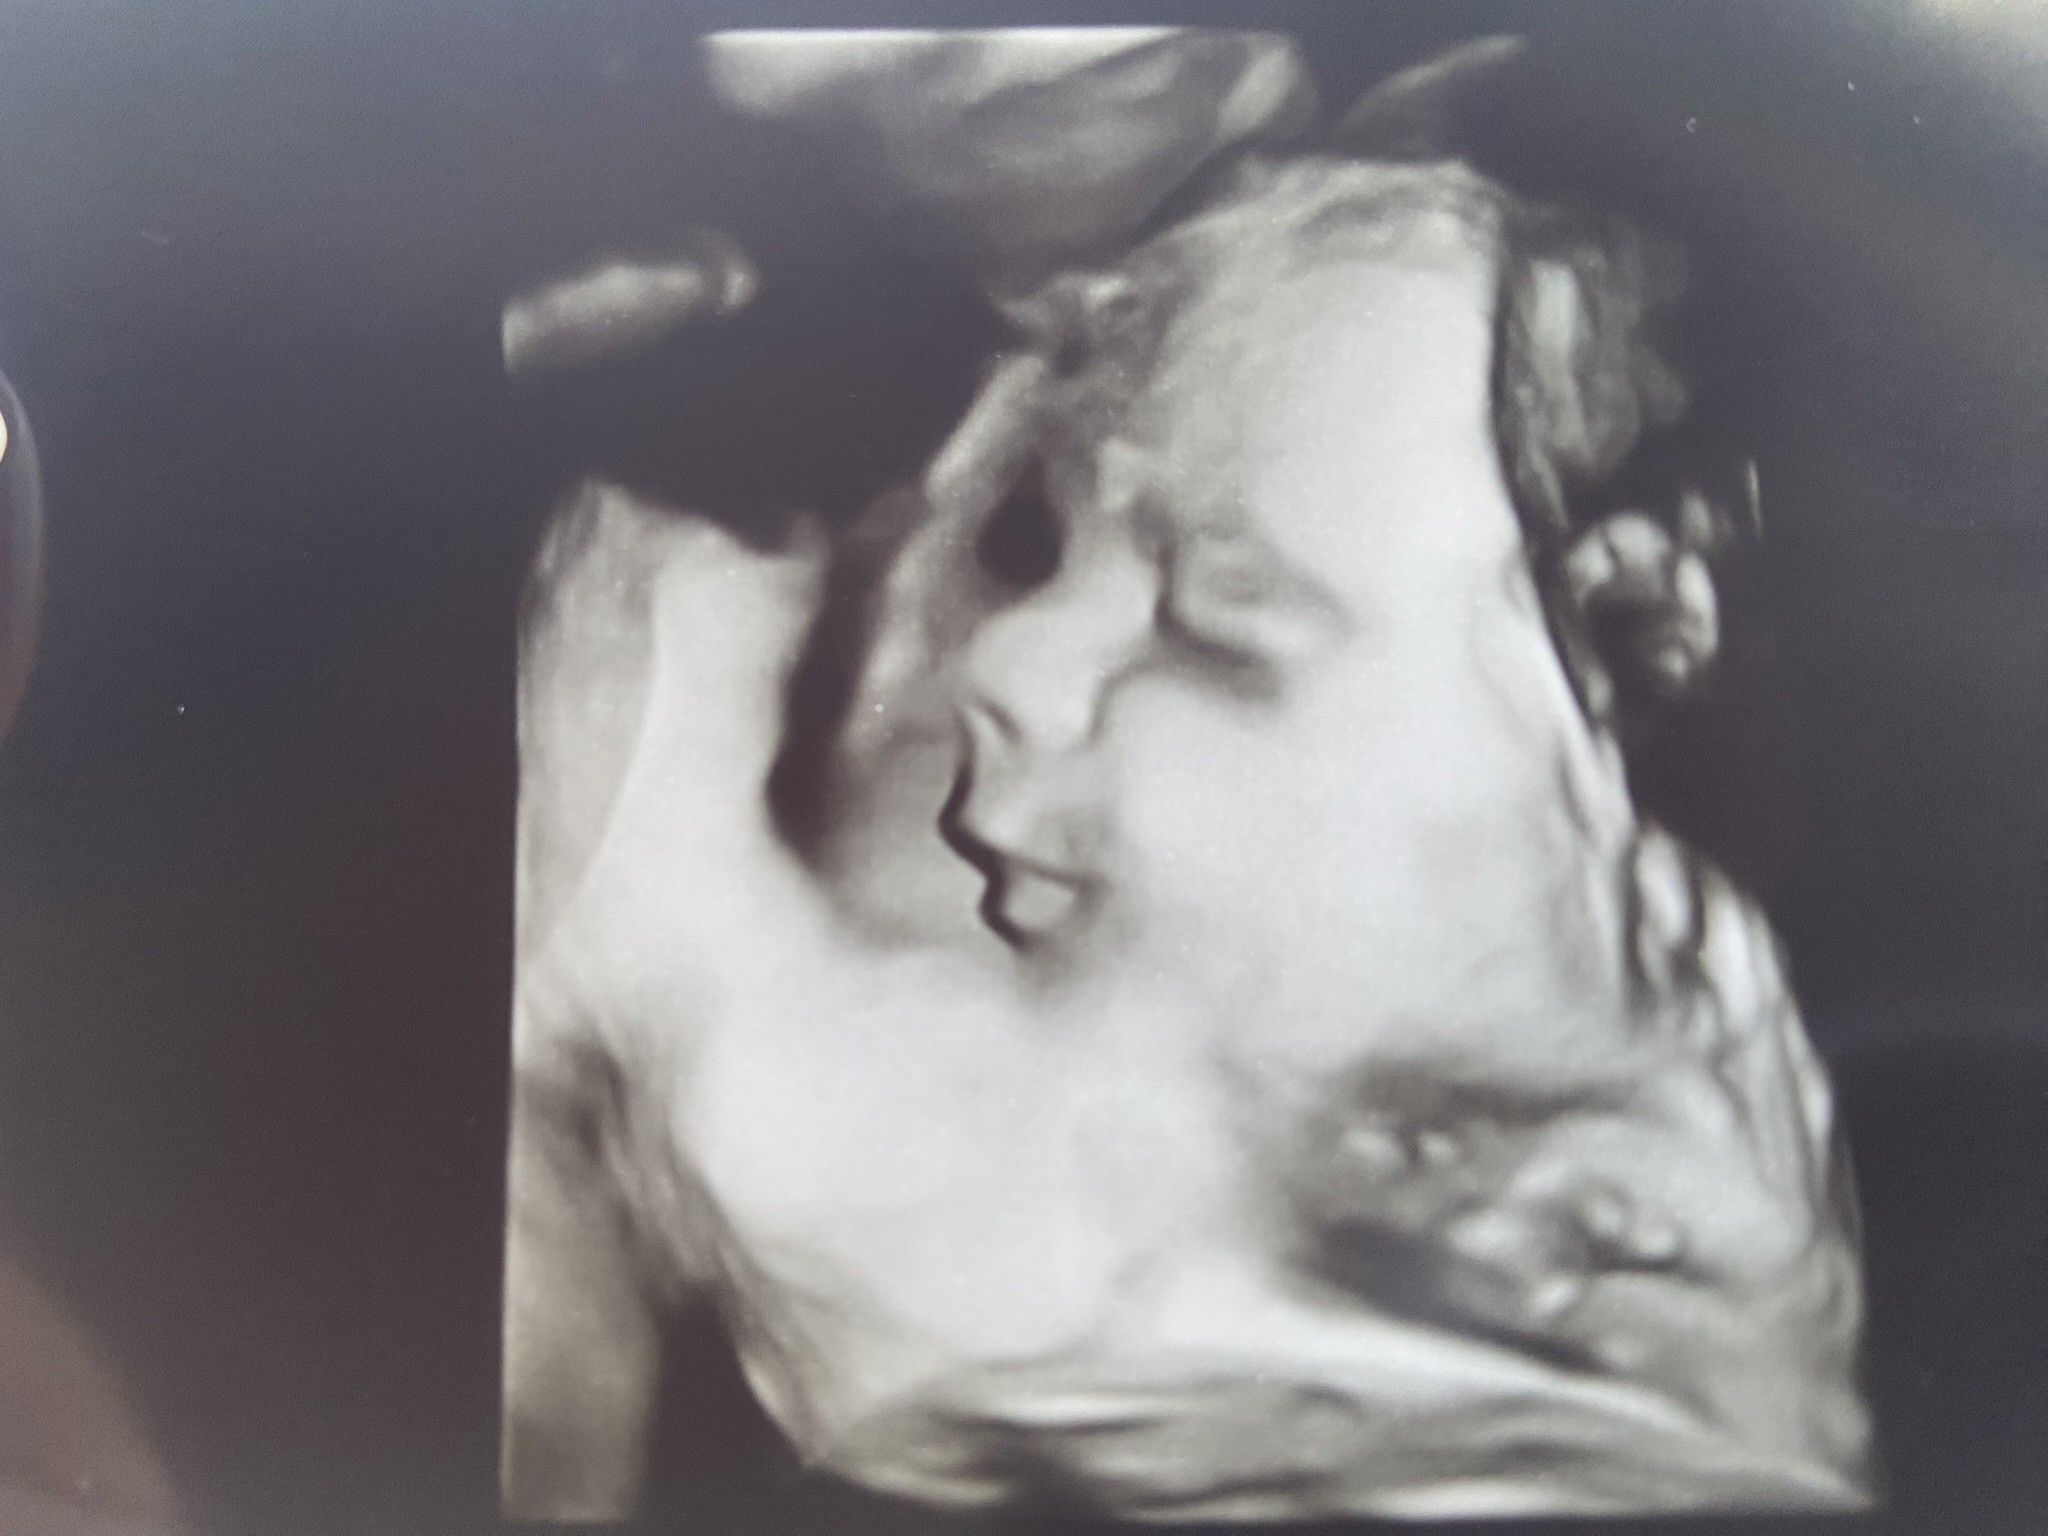

Dobrze u Nas, 2 tyg temu byliśmy u lekarza i maluszek ważył 1,2 kg 🥰 rośnie mój mały króliczek 🤍🥰🤭 - w załączniku zdj 🫶🏻

W nast tyg idziemy na ostatnie prenatalne, ale wierze ze wyjdą tez Ok. No i zobaczę maluszka w 4-5D 🤭

Załączniki

• C3841BE5-56E7-4F98-B16E-09A20C90CE3F.jpeg

C3841BE5-56E7-4F98-B16E-09A20C90CE3F.jpeg

431,3 KB · Wyświetleń: 109